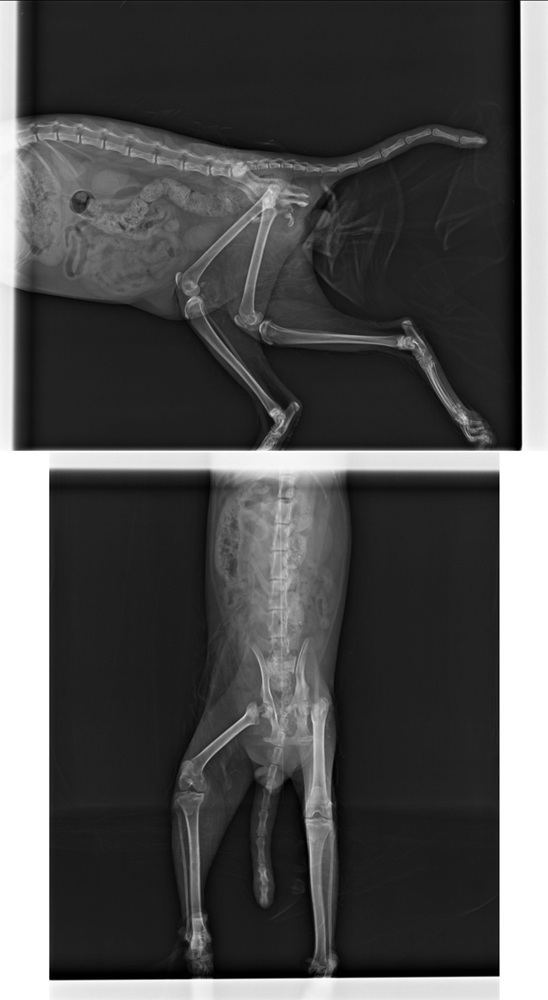

醫生診斷後,發現疑似車禍造成尾巴潰爛.左後肢肌肉萎縮,在X光下也看出雙側股骨頸有骨折

2014.01.09 因為斯文年紀還輕,手術後萎縮的肌肉可望復原,於是評估後進行了第二項手術-雙側股骨頭切除,手術完當天,斯文就有自己吃飯,隔天排泄也正常,都會自己走到旁邊上廁所

X-RAY 400*2